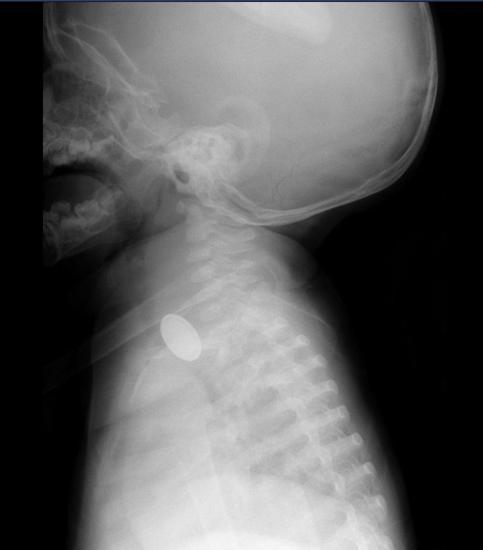

Kayseri'de 15 aylık A.Y.Ç.'nin yemek borusuna, evde oyun oynadığı sırada düğme pil ve lego oyuncak parçası kaçtı. O sırada yanında olan 4 yaşındaki kardeşi, 'Kardeşim lego yuttu' diyerek annesini çağırdı. A.Y.Ç.’nin ağızına bakan anne Tuğba Yılmaz, parçayı göremeyince dışkısından çıkacağını düşündü. Bir süre sonra A.Y.Ç.'nin yutma güçlüğü çektiğini gören Tuğba Yılmaz, Kayseri Şehir Hastanesi'ne başvurdu. A.Y.Ç.'ye yapılan röntgende, yemek borusunda düğme pil ve lego parçası oyuncağa rastlandı. Kız bebek A.Y.Ç., Kayseri Şehir Hastanesi Çocuk Cerrahisi ve Ürolojisi Anabilim Dalı Başkanı Doç. Dr. Mustafa Erman Dörterler ve ekibi tarafından ameliyata alındı. Yaklaşık 3 saatlik süren operasyonun ardından A.Y.Ç.'nin yemek borusuna kaçan düğme pil ile lego oyuncak parçası çıkarıldı.

Kayseri Şehir Hastanesi Çocuk Cerrahisi ve Ürolojisi Anabilim Dalı Başkanı Doç. Dr. Mustafa Erman Dörterler, "Hastamız 15 aylık bir bebek. Hastamız, disk pil ve beraberinde bir lego parçası yutmuş. Ben gece 01.30 gibi hastaneye geldim. Pili ve lego parçasını yutmasının üzerinden yaklaşık 6-7 saat geçmişti. Bu durumlarda dakika ve zaman çok önemli. 2 saatten sonra çok ciddi sıkıntılar oluşturabilecek hatta ölümle sonuçlanabilecek durumlarla karşı karşıya kalmaktayız. Ben, göğüs cerrahisi, çocuk gastroenteroloji, anestezi ekibi ve yardımcı sağlık personelleriyle beraber yaklaşık 20-25 kişiydik. Çocuğa, hızlı ve dikkatli bir şekilde müdahale ettik. Çünkü zaman ilerlediği için disk pil, yemek borusuna yapışmış ve delmek üzereydi. Dikkatli şekilde özenerek çıkarmaya çalıştık. Ekip çalışmasıyla beraber çıkarmayı başarabildik. Çocuğumuzun yoğun bakımdaki 2 günlük takip süreci devam ettikten sonra servisimize aldık. Şu an gayet iyi" diye konuştu.